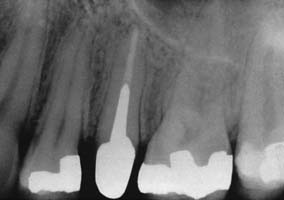

On occasion, an existing post and core must be removed (e.g., for re-treatment of a failed root canal filling). Patients must understand in advance that post removal is a risky process and occasionally results in radicular fracture. If sufficient length of post is exposed coronally, the post can be retrieved with thin-beaked forceps. Vibrating the post first with an ultrasonic scaler weakens brittle cement and facilitates removal. A thin scaler tip or special post removal tip is recommended (Fig. 12-47). Although histologic examination with animal models reveals no harmful effect in the periodontal tissues,86 ultrasonic removal is slower than other methods and may result in an increased number of canal and intradentin cracks.87 Alternatively, a post puller can be used.88 This device consists of a vise to grip the post and legs that bear on the root face. A screw activates the vise and extracts the post.

Fig. 12-47 Post removal by ultrasonic device. A, Preoperative radiograph of the left maxillary first premolar with a parallel-sided threaded post that had to be removed for endodontic retreatment. B, After the coronal portion of the post has been well isolated, the tip of the ultrasonic device is placed against it, and energy is applied to disrupt the cement interface. Note the suction tip, which removes water spray used with the ultrasonic handpiece. C, After a time, the post becomes loose within the canal and can be retrieved by forceps. D, Radiograph of the premolar after post removal.

(Courtesy of Dr. L. L. Lazare.)